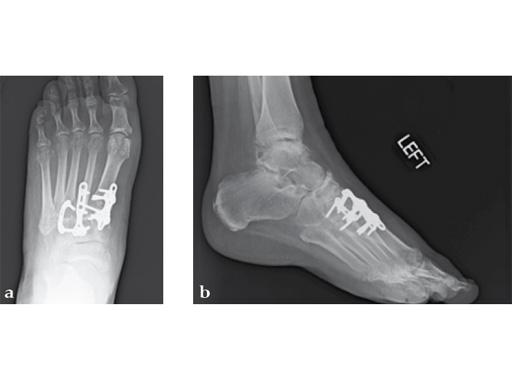

A 38-year-old man presented for opinion after two attempts to fuse the big toe MTP joint. The AP view is significant for luscency at the joint line. The lateral view is notable for loosening of the hardware and malposition because of the dorsiflexion built in to the precontoured implant. Revision was planned using a 0 variable angle locking/compression hallux MTP plate.

At 10 weeks postoperatively (see Fig. 2ab) the patient had no pain with weight bearing. The lateral view demonstrates improved position of the toe using a 0angle plate.